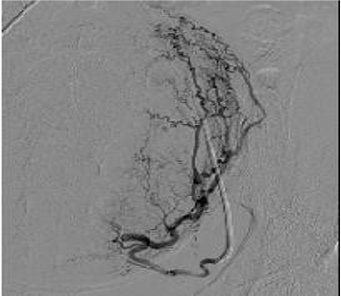

导管技术与子宫肌瘤相似,但是血管栓塞的终点应该是完全造影剂停滞【Lohle et al. 2007】

- 类似于UFE的导管技术,相似栓塞剂,充分子宫动脉水平段停滞作为适当的血管造影栓塞终点

50岁,严重经期出血 栓塞 微球400μm ,每侧2ml,然后改 500μm 每侧1ml

3个月后随访,经期出血减少